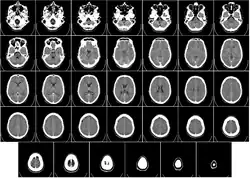

Głowa

Tomografia komputerowa jest obecnie podstawowym badaniem obrazowym pozwalającym na uwidocznienie struktur śródczaszkowych. Powinna być wykonana jak najszybciej w przypadku udaru mózgu w celu zróżnicowania pomiędzy udarem niedokrwiennym i krwotocznym. Pozwala też wykryć obecność guza śródczaszkowego albo krwiaka pourazowego.